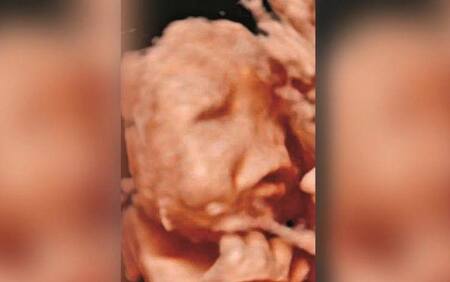

El programa Rua segura, de Correio da Manha, brindó una entrevista a la familia y la primera foto de la criatura, en la que se lo puede ver junto a su hermana mayor. También mostró postales con sus padres e, incluso, una de las polémicas ecografías.

Durante la entrevista, los padres de Rodrigo mostraron uno de los ultrasonidos que les hizo el obstetra Artur Carvallo, que los atendió durante todo el embarazo y que jamás se dio cuenta de las malformaciones en el feto.